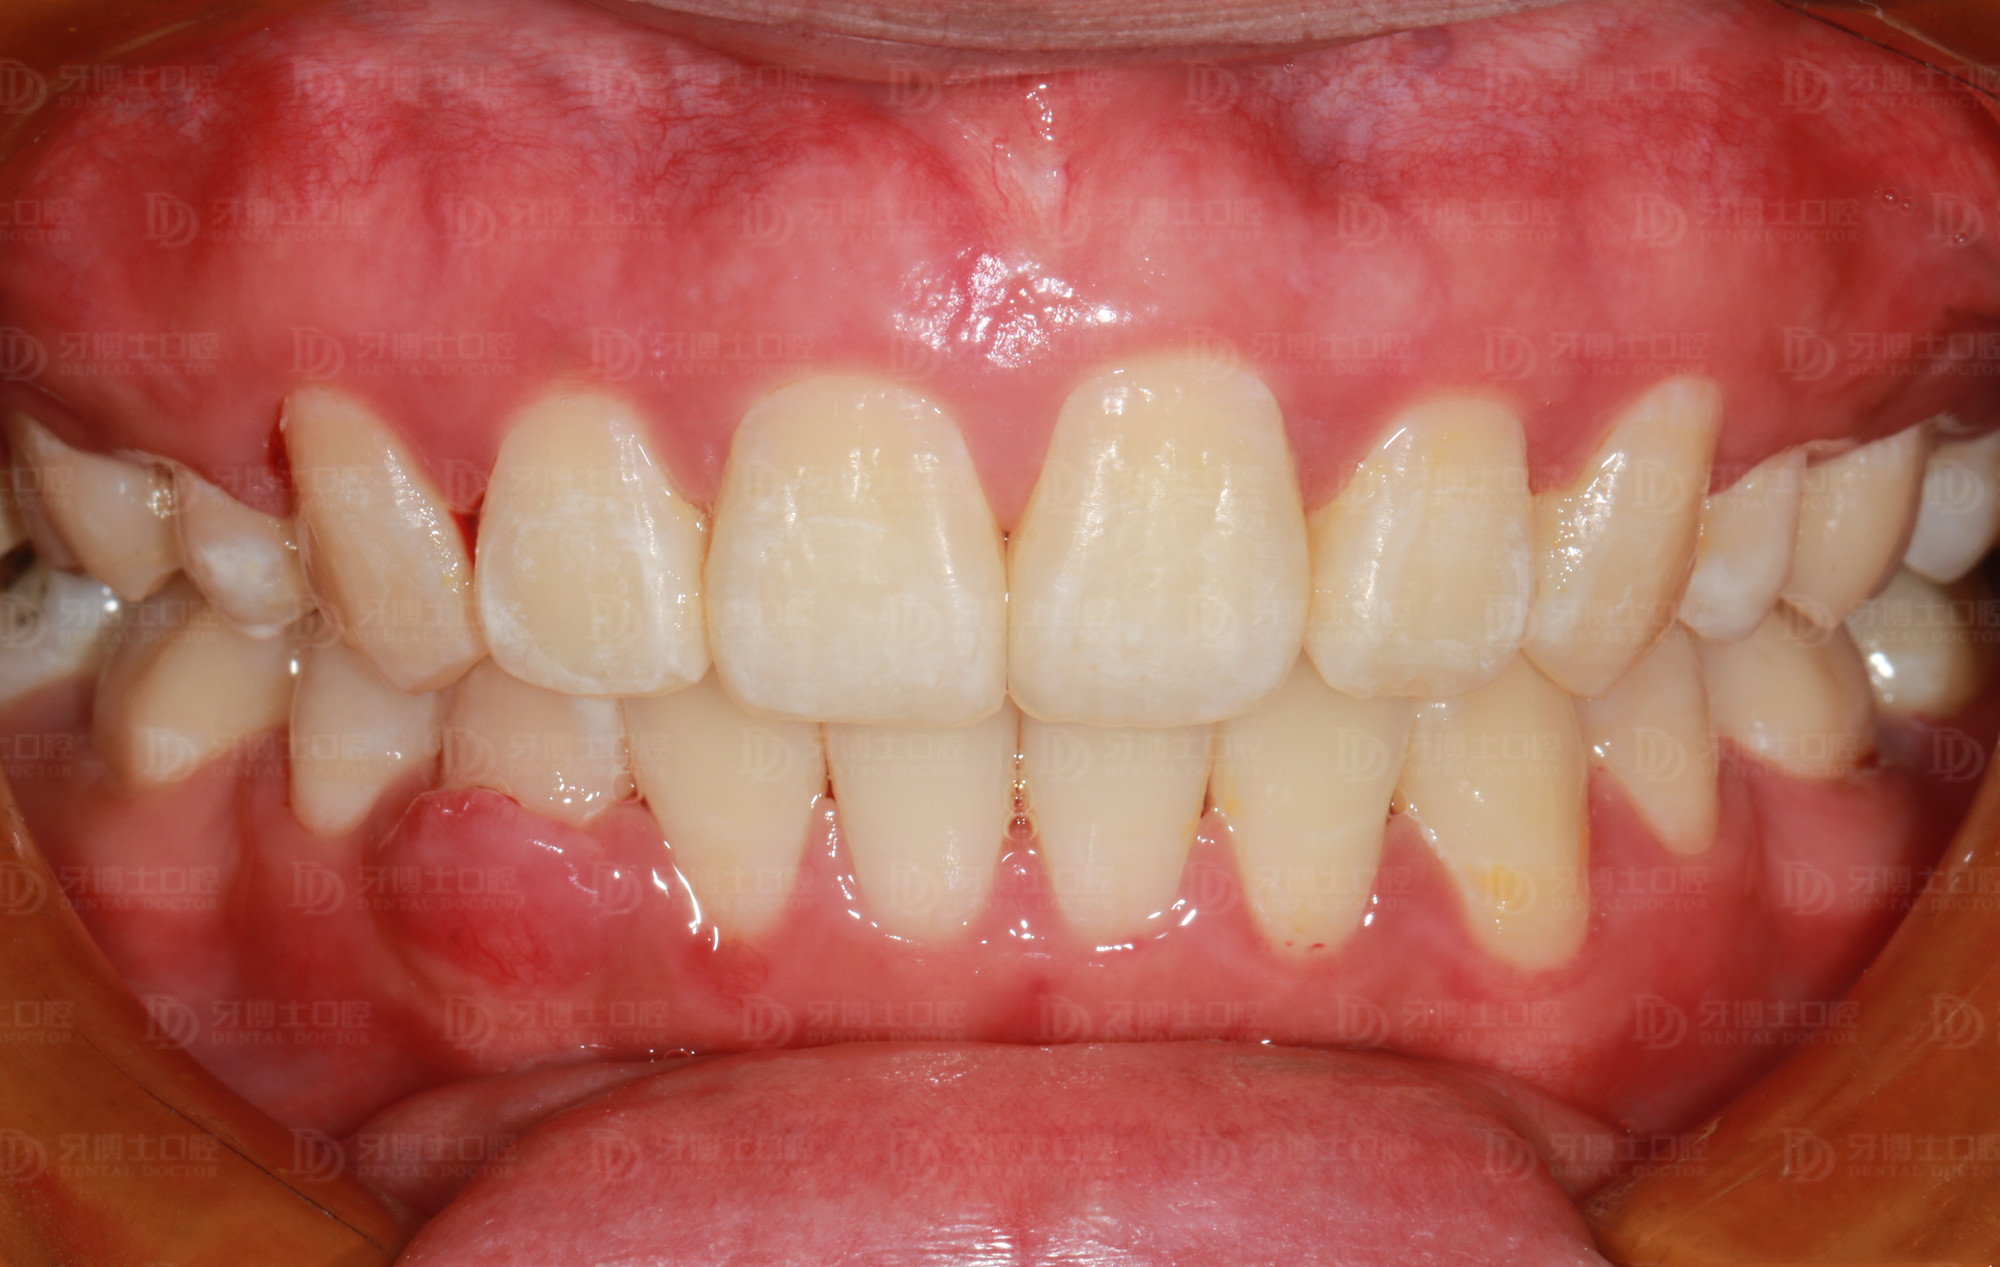

矫正后

牙齿排齐内收,更易清洁了,牙周问题明显改善很多,面部整体美观度增加,笑容更加自信。